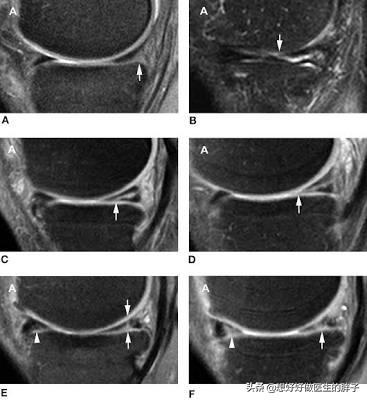

半月板损伤一般根据根据核磁的影像学表现我们将之分为三度。

一度损伤呢,是半月板最轻微的损伤,半月板的内部结构会有一些损伤信号在核磁当中表现出来,但是患者一般不会有特殊的症状。

二度损伤,半月板的内部就会有明显的软骨损伤,而且范围会相对来讲比较大,但是损伤部位的软骨并没有达到半月板的表面,也就是说半月板整体的形态是非常好的,但是内部的结构会有异常。

三度损伤,就是比较重的半月板撕裂了,也就是说半月板的整体结构有了改变,当这种情况而已发生以后,就会刺激到关节腔周边的滑膜,导致滑膜出现炎症。(以下是半月板的三度损伤的核磁影像图,和半月板撕裂继发滑膜炎的术中所见,大家一看就会明白)